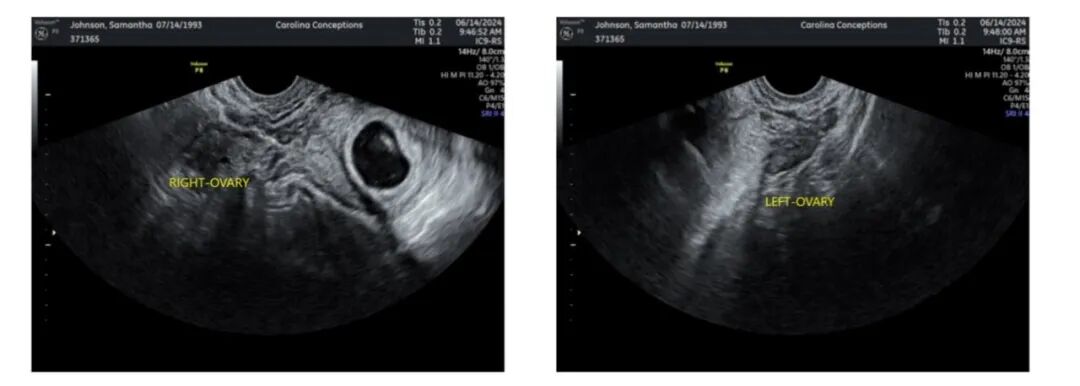

爱妈B的双胎宝宝健康成长中!宝宝们目前已有十周零六天大。我们准父母这次在捐卵女生的帮助下,成功培育出高品质的胚胎,两个宝宝均顺利着床。爱妈B将转至当地妇科诊所继续监控宝宝们的健康发展。

爱妈S在首次B超检查来了!已能听到宝宝强有力的心跳,尽管宝宝还很小。准父母对此感到无比激动,他们特别期待属龙的宝宝,并已成功匹配了两位代母,另一位爱妈的妊娠也在顺利进行中,满怀期待宝宝们继续健康成长。